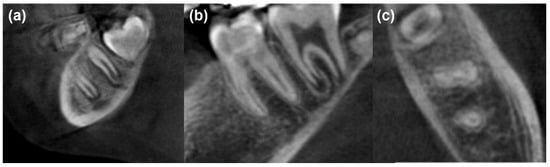

| Criteria/Group | MM-MTA (G1) | Nano-Hydroxyapatite (G2) | PRF (G3) | Statistical Analysis |

|---|---|---|---|---|

| Age (years) | 8.6 ± 2.0 | 8.8 ± 1.8 | 8.8 ± 2.1 | p = 0.911 |

| Sex females (%) | 11 (55) | 10 (50) | 9 (45) | p = 0.819 |

| Apical closure complete (6 months) (%) | 5 (25) | 3 (15) | 4 (19.04) | p = 0.726 |

| Apical closure complete (12 months) (%) | 10 (50) | 11 (55) | 12 (60) | p = 0.817 |

| Canal obliteration (6 months) (%) | 3 (15) | 4 (20) | 0 (0) | p = 0.111 |

| Canal obliteration (12 months) (%) | 7 (35) | 9 (45) | 1 (5) | p = 0.014 * |